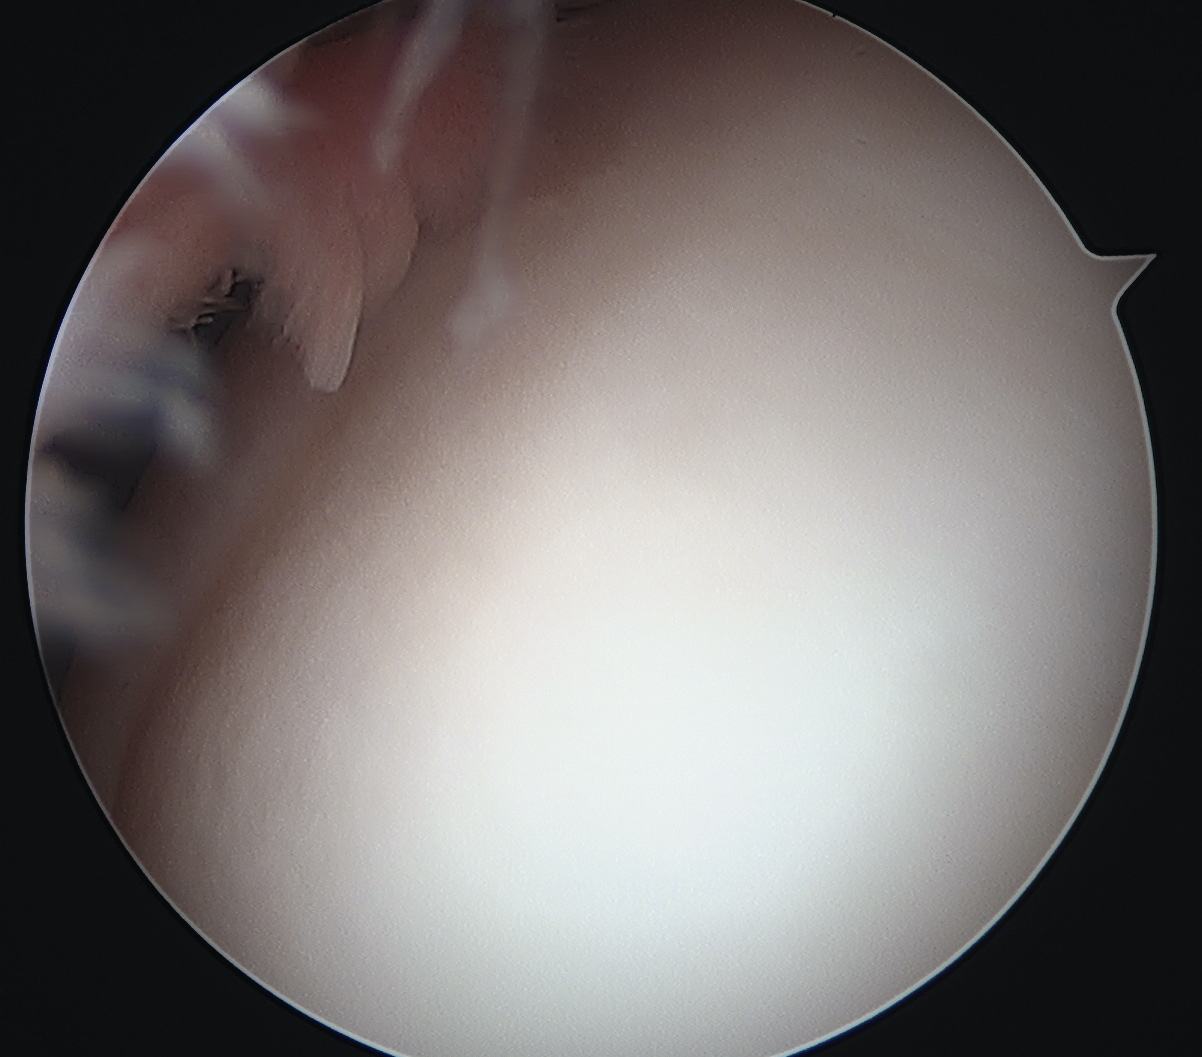

Arthroscope in lateral portal

Clear fat pad

Ensure can see entire dimensions of OCD

Arthroscope in medial portal